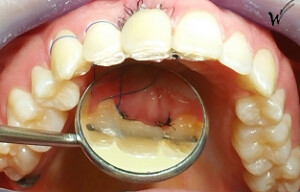

Situation clinique initiale avant traitement

L'extraction de cette dent

En raison de problèmes de rhizalyse, une résorption pathologique de la racine, ainsi que d’une infection, l’incisive centrale du patient a été extraite.

Lors de cette extraction, des biomatériaux (substituts osseux) ont été utilisés pour combler l’alvéole vidée. Il était également essentiel de réparer ou de renforcer la paroi externe de cette alvéole pour prévenir sa résorption. La finesse de cette paroi autour de la racine naturelle de l’incisive (quelques dixièmes de millimètres) ne permettait pas la pose d’un implant seul, compte tenu du vieillissement des tissus environnants et de l’importance de l’esthétique à ce niveau.